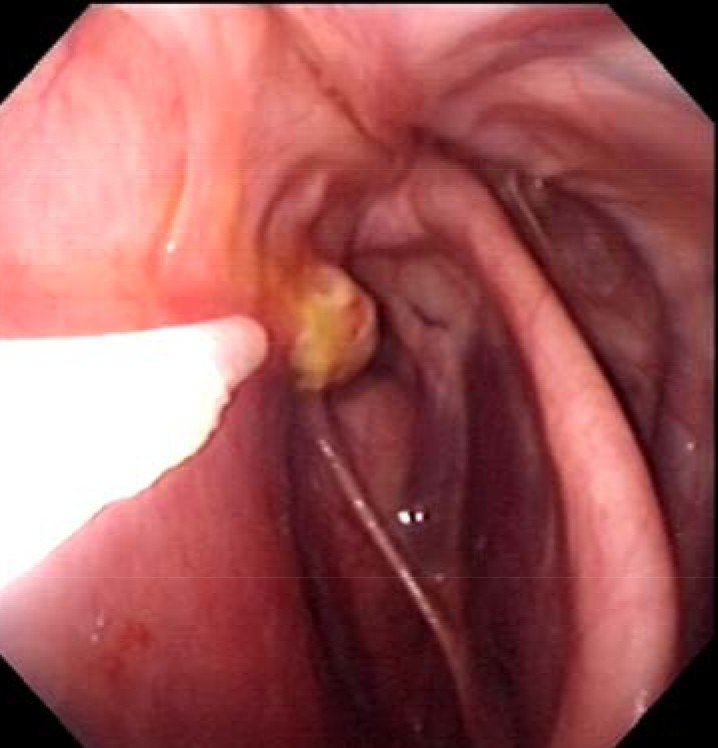

les poches après les 10 jours en clinique